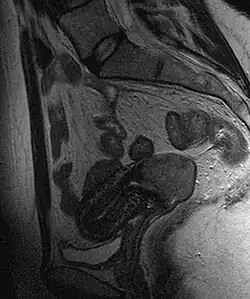

Often, before the biopsy, the doctor asks for medical imaging to rule out other causes of a woman's symptoms. Imaging modalities such as ultrasound, CT scan, and MRI have been used to look for alternative disease, spread of the tumor, and effect on adjacent structures. Typically, they appear as heterogeneous masses on the cervix.[64]